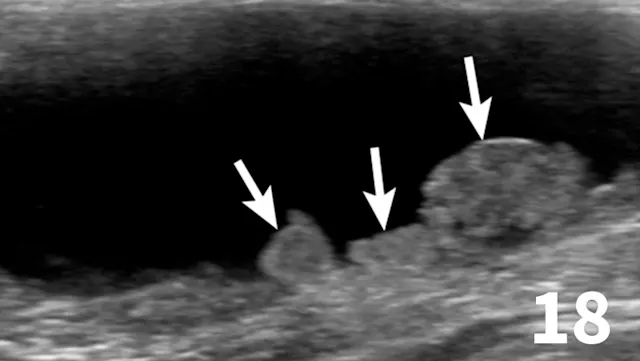

Survey radiographs of the urinary bladder are helpful for evaluation of size and location and for detection of radiopaque calculi. Urinary bladder distention is readily detected (Figure 17). Radiographs are of limited value in evaluating mural disease because the bladder wall cannot be differentiated from the fluid contained within the bladder. Bladder wall thickening (eg, bacterial inflammation, polypoid cystitis, neoplasia) is best evaluated by ultrasonography or double-contrast cystography (Figure 18). It should be noted that the degree of bladder filling can affect bladder wall thickness. For example, a small, mildly distended bladder may appear to have a thickened bladder wall on ultrasound compared with a moderately or severely distended bladder (Figure 19). This potential disadvantage can often be overcome by reevaluating the bladder several hours after preventing voiding.

Double-contrast cystography can be an excellent tool to evaluate bladder wall thickness and any irregularities of the bladder mucosal surface and to rule out the presence of radiolucent cystouroliths (Figure 20). Although double-contrast cystography is more invasive because of the need for urethral catheterization, artifactual bladder wall thickening is usually not an issue because the degree of bladder distention can be controlled.